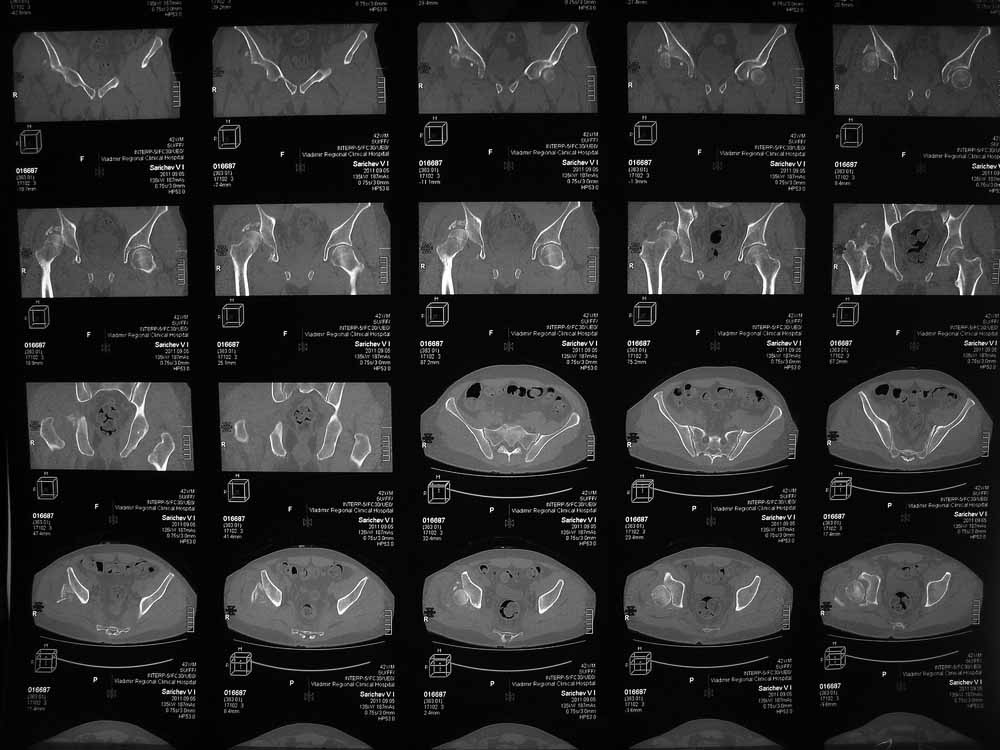

42 года, майор запаса. Травма от 20.06 - ДТП. Лечился в гражданском ЛПУ. Вывих бедра диагностирован только 4 недели спустя. "Тянулся", неоднократно - попытки закрытой репозиции. Попытка открытой репозиции - без результата. Потом опять пытались закрыто, сказали, что вправили, тянулся. После снятия ССВ - опять вывих. Поступил к нам. Сейчас - СРБ больше 10, в ОАК - воспаление. Местно - головка кзади и кверху, укорочение 7, голова подвижна. Отек, незначительная боль в в/3 бедра. Пассивно из наружной ротации выводится, активных движений в ноге нет. Рубец по наружной поверхности верхней трети бедра, без воспаления. Каким образом выполнялось открытое вправление - данных нет. Окончательно снят с вытяжения 2 недели назад.

Структуру головки не очень хорошо видно, есть перелом нижнего отдела головки БК, сломанный задний край небольшой. Срок после травмы 4 недели, молодой возраст. Есть смысл синтезировать ВВ, а дальше посмотреть. Будут проблемы - легче будет протез ставить, ну а если лет 8-10 сустав поработает, то и это хорошо. Если вы уж решили делать протезирование, не мудрите, вполне можно обойтись стандартной вертлужной впадиной с укреплением ее винтами.

Вот еще сканы.